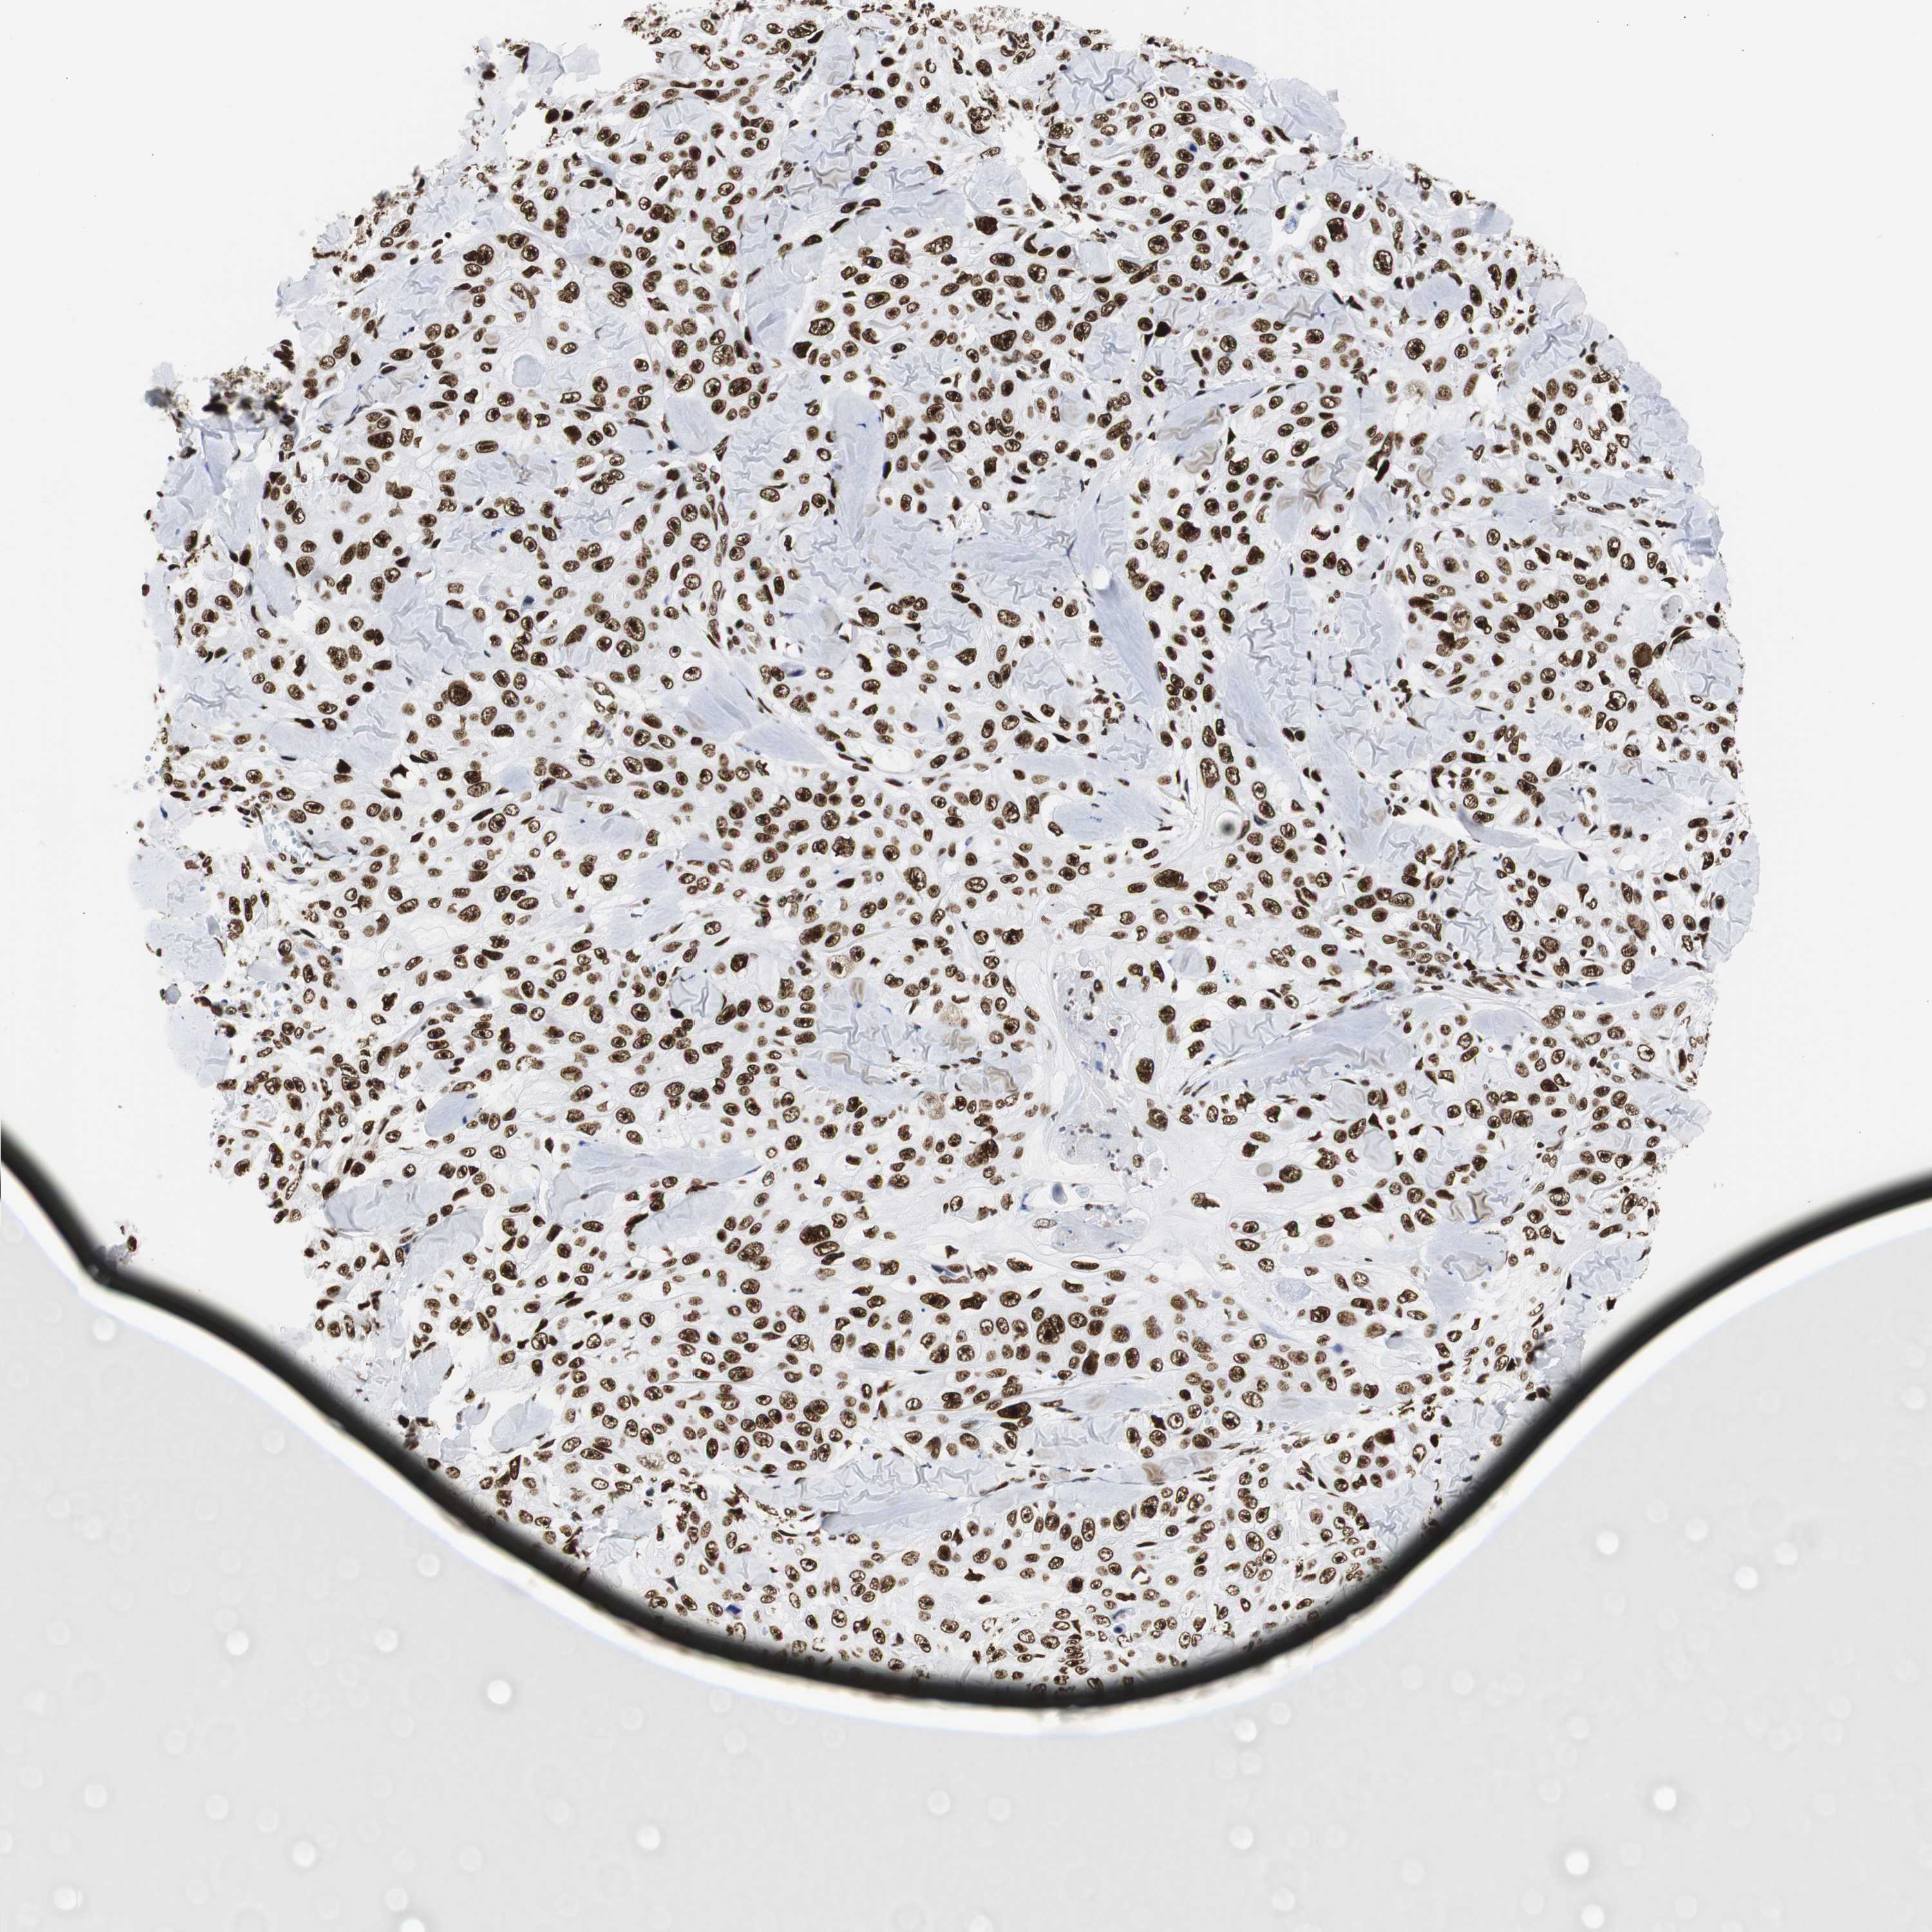

SKIN CANCER - Protein expressioni

A mouse-over function shows sample information and annotation data. Click on an image to view it in a full screen mode. Samples can be filtered based on level of antibody staining by selecting one or several of the following categories: high, medium, low and not detected. The assay and annotation is described here.

Each image is clickable and will lead to virtual microscopy that enables deeper exploration of all samples and also displays staining intensity scores, fraction scores and subcellular localization as well as patient and tissue information for each sample.

Antibody CAB004436

Staining

High

Medium

Low

Not detected

Intensity

Strong

Moderate

Weak

Negative

Quantity

>75%

75%-25%

<25%

None

Location

Nuclear

Cytoplasmic/membranous

Cytoplasmic/membranous,nuclear

Squamous cell carcinoma, NOS

Basal cell carcinoma

Squamous cell carcinoma in situ, NOS

Squamous cell carcinoma, metastatic, NOS

Adnexal tumor, benign

Papilloma, NOS